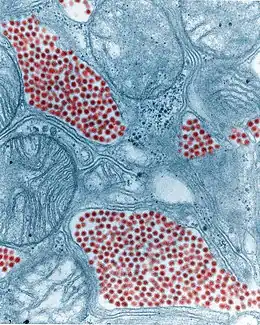

| Colourised TEM micrograph of a mosquito salivary gland: The virus particles (virions) are coloured red. (83,900x magnification) | |